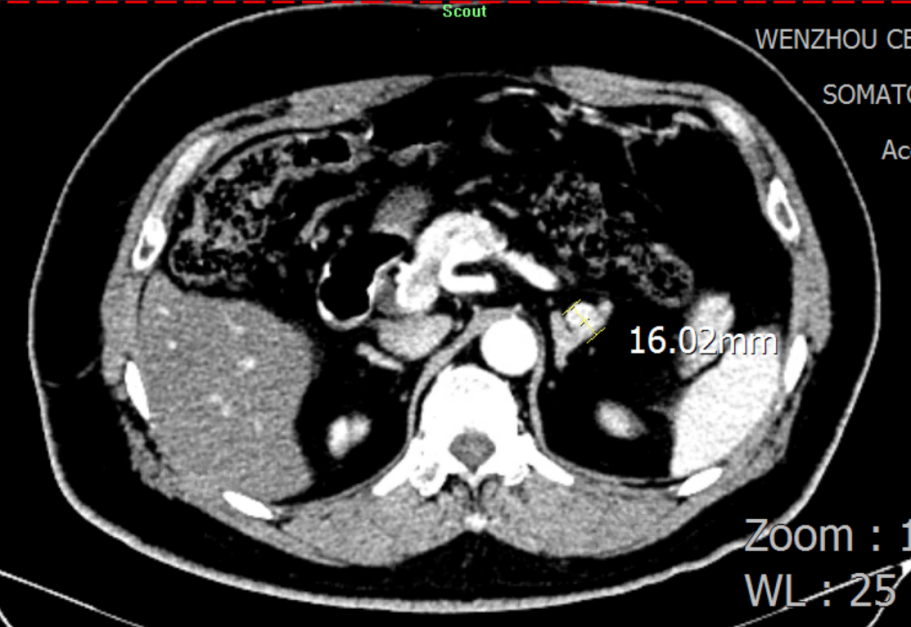

图片3.png

肾上腺增强CT:思量左侧肾上腺结节状增生

“从卧位变为立位 ,,,, ,,, ,检测报告显示 ,,,, ,,, ,患者的醛固酮水平没有像康健人群一样升高 ,,,, ,,, ,反而下降了。。。。。。因此 ,,,, ,,, ,我们推测他是可手术治愈的原醛症-醛固酮瘤患者。。。。。。”果真 ,,,, ,,, ,CT效果进一步佐证了余主任的诊断。。。。。。